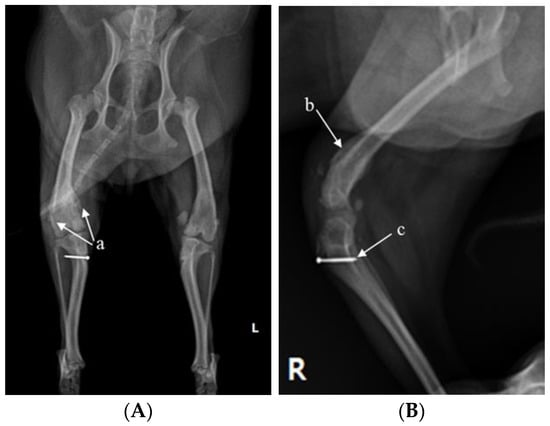

X-ray (E7239X, TOSHIBA, Tokyo, Japan) analysis was conducted. According to radiograph imaging (Weview pacs system, Seoul, Republic of Korea), the screw fixing the bone fragment to the tibial tubercle in the right hind limb had remained, and the patella was not recognized in the radiography view, which was consistent with the results following palpation (Figure 1A,B). Bone proliferation was noted, and edema was observed around the stifle joint (Figure 1A,B). Severe MPL, periostitis, and edema around the stifle joint in the left hind limb were observed (Figure 1A,C). Following a physical examination, complete blood count (Procyte Dx analyzer, Maine, USA) and biochemistry device (Catalyst One chemistry analyzer, Maine, USA) were measured. Neutrophil levels were observed to be slightly increased, namely, 11.71 μL (78.2%), suggesting that inflammatory responses were in progress (Table 1).

Figure 1.

A 2-year-old Pomeranian dog with chronic weight-bearing lameness of the stifle joints in both hind limbs. (A) Craniocaudal radiographic views of the stifle joints of the dog. (B) Lateral radiographic views of the right stifle joints. (C) Medial radiographic views of the left stifle joints. a: osteophyte, b: periostitis, c: residual screw for tibial tuberosity transposition, d: periostitis, R: right, and L: left.